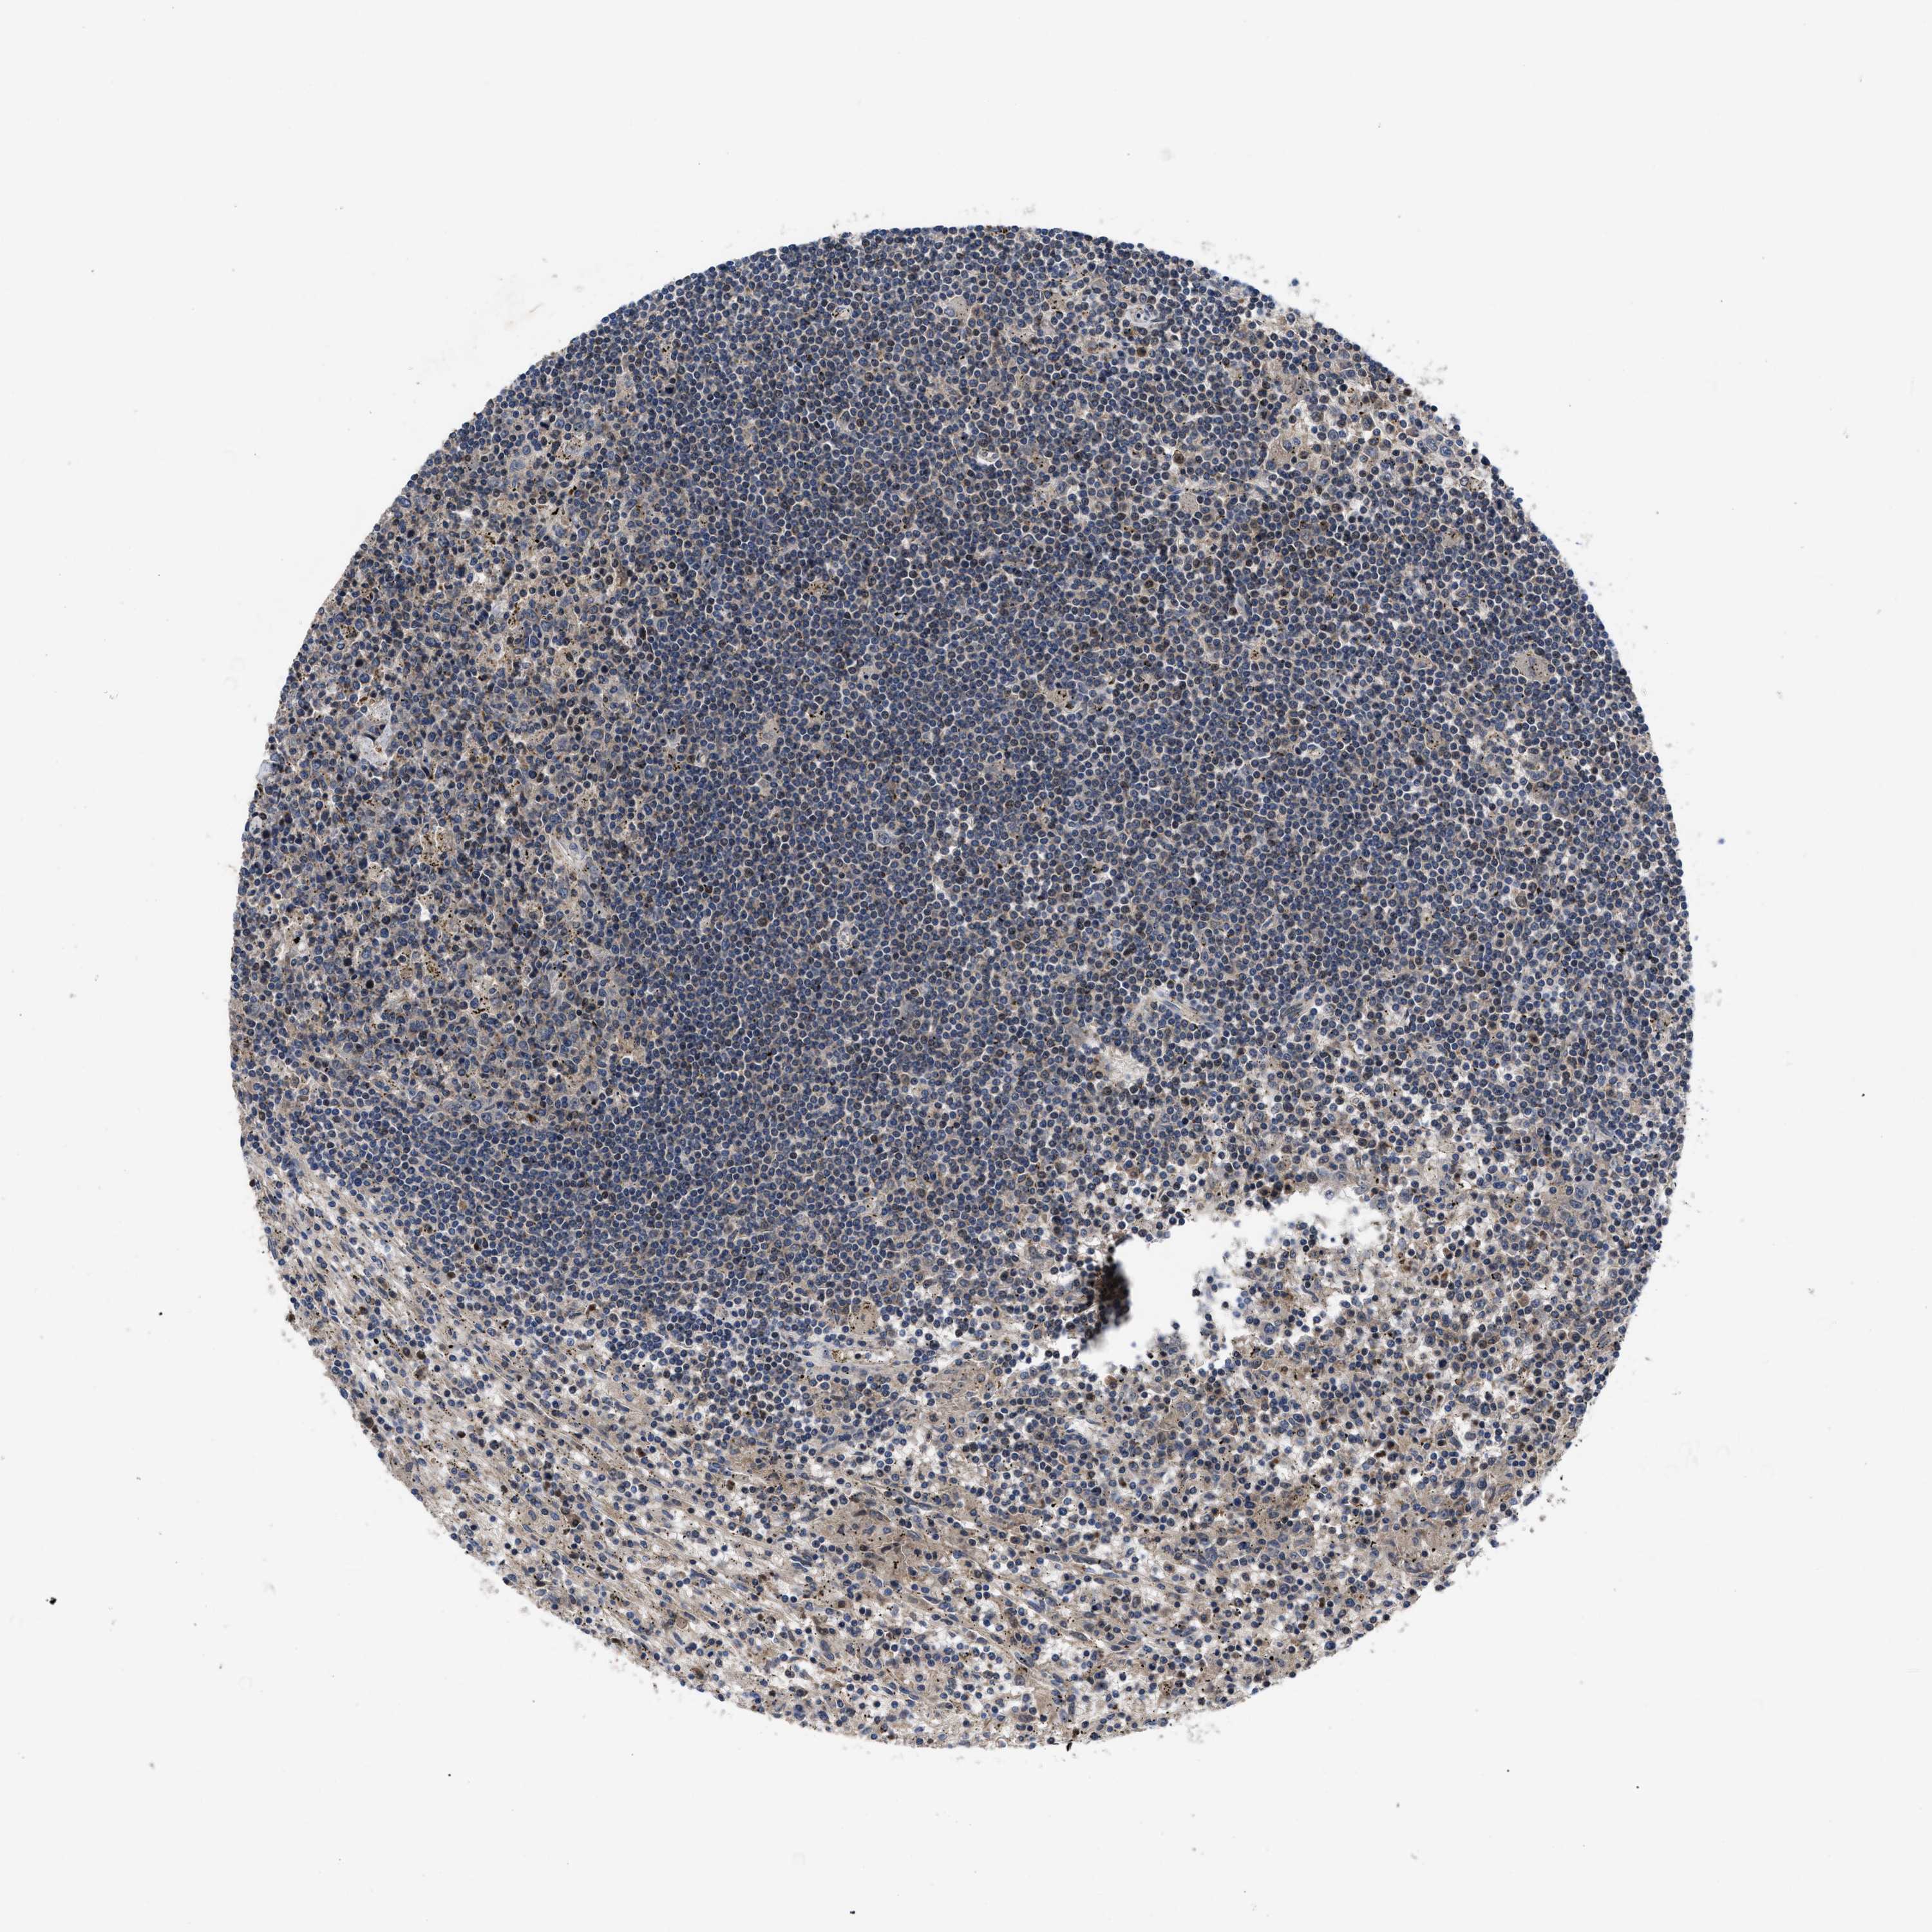

LYMPHOMA - Protein expressioni

A mouse-over function shows sample information and annotation data. Click on an image to view it in a full screen mode. Samples can be filtered based on level of antibody staining by selecting one or several of the following categories: high, medium, low and not detected. The assay and annotation is described here.

Antibody stainingi

Antibody staining in the annotated cell types in the current human tissue is reported as not detected, low, medium, or high, based on conventional immunohistochemistry profiling in selected tissues. This score is based on the combination of the staining intensity and fraction of stained cells.

Each image is clickable and will lead to virtual microscopy that enables deeper exploration of all samples and also displays staining intensity scores, fraction scores and subcellular localization as well as patient and tissue information for each sample.

Antibody HPA018162

Staining

Medium

Intensity

Weak

Quantity

75%-25%

Location

Nuclear

Hodgkin's disease, NOS

Malignant lymphoma, non-Hodgkin's type, High grade

Malignant lymphoma, non-Hodgkin's type, Low grade